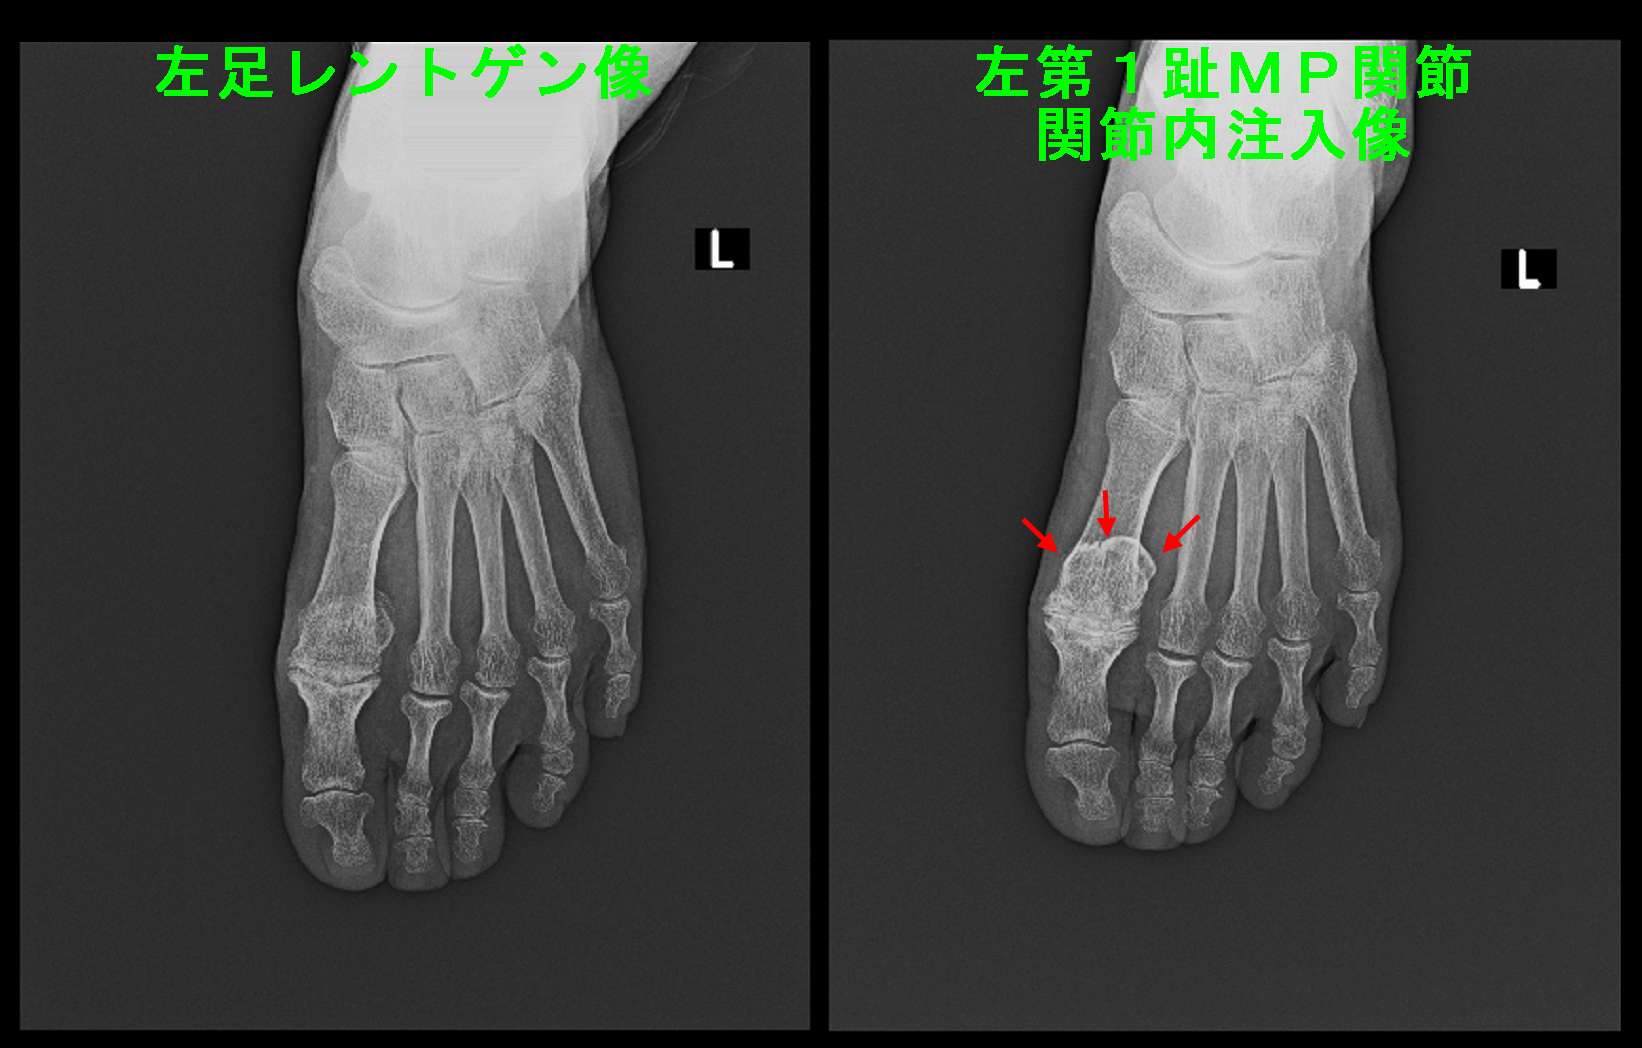

ステロイドの関節内注入では治癒にもっていくことができないと判断し治療方針を変えて、注入薬剤をステロイドから変形性膝関節症で適応されている変形老化予防のヒアルロン酸製剤に変更して、1週間に1回連続5回関節内注入してみましょうと提案し、了承をえました。

67才女RA Xp3.jpg

令和7年10月28日からヒアルロン酸の関節内注入を開始し、11月25日に5回目の注入を行いました。以後は2週に1回で継続しましたが、令和8年1月6日には痛みはVAS0~1ということでヒアルロン酸の関節内注入は経過をみることにしました。

レントゲン像では左第1足指のMP関節は関節の隙間はかなり狭く、骨の端はとがっていて中等度~重度の変形性関節症の所見です。この患者さんにヒアルロン酸の関節内注入を施行してみました。

1週後の10月14日にはVAS6の歩行痛は0となりました。2度目のヒアルロン酸の関節内注入は行いましたが、当初予定した5回の連続の注射は2回で終了となりました。